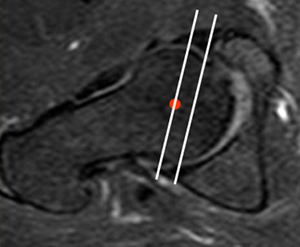

Con RM se puede valorar en un corte axial oblicuo. Se traza una línea que una el reborde oseo anterior y posterior y otra línea paralela a esta, que pase por el centro de la cabeza femoral. Normalmente la línea del centro femoral, tiene localización lateral. En los casos de coxa profunda, la línea se localiza medialmente. (Fig 95 y 96).

Fig 95. Coxa normal.

RM axial oblicua. La paralela al centro de la cabeza femoral se localiza lateral, a la línea que une el reborde acetabular oseo anterior y posterior.